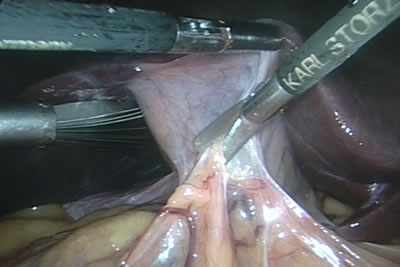

Операция: Лапароскопическая

забрюшинная паракавальная лимфаденэктомия справа, радикальная

нефрэктомия справа

Диагноз: Семинома правого

яичка T1NхM0. Почечно-клеточный рак справа T1bNxM0

Оперирует: Профессор, Пучков

Константин Викторович (Рязань).